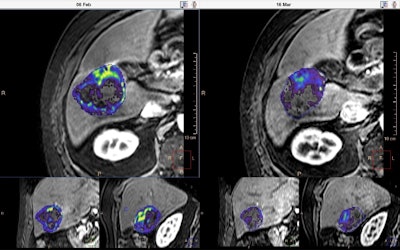

Philips is presenting IntelliSpace Portal 8.0, the latest edition of its advanced data sharing, analytics and visualization platform that helps radiologists detect, diagnose, and follow up on treatment of diseases. This technology helps address the changing demands in radiology that result from an increasing prevalence of cancer and its rising economic toll. The latest system offers a number of new features such as fast 3D quantitative renderings of tumors, in a fully integrated oncology suite to improve diagnostic confidence and patient care.

The oncology suite complements the range of applications offered by the existing platform. It will help clinicians to visualize, diagnose, and measure disease states and communicate across modalities, with one efficient, automated, and guided workflow, stated the company. The latest release now boasts more than 68 clinical applications for seven diagnostic modalities, including CT, MRI, ultrasound, mammography, and interventional x-ray.